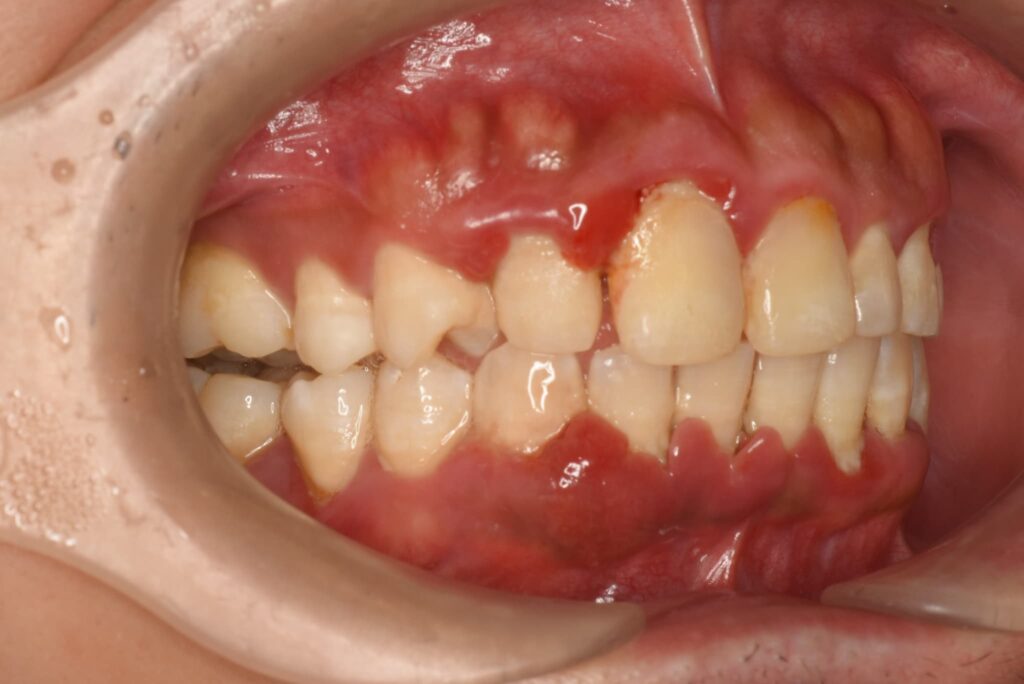

そもそも、健康な歯ぐきからは、ブラッシング程度で血が出ることはありません。 健康な歯ぐきは薄いピンク色をしていて、引き締まっており、歯と歯の間の三角形の隙間をきれいに埋めています。

しかし、歯ぐきに炎症が起きると、話は変わります。 炎症が起きると、体はその部分の悪い細菌を退治しようとして、血液をたくさん送り込みます。その結果、血管が膨らみ、少しの刺激(ブラッシングや食べ物)でも破れやすくなってしまうのです。

つまり、「血が出る=そこに炎症がある=体が細菌と戦っている」という証拠なのです。

2. 出血の大きな原因「歯周病」の正体

歯ぐきから血が出る原因の多くは「歯周病」です。 歯周病は、一言で言うと「歯を支える土台が溶けてしまう病気」です。

・歯肉炎(しにくえん): 歯ぐきだけに炎症が起きている状態。

・歯周炎(ししゅうえん): 炎症が深まり、歯を支える骨(歯槽骨)まで破壊され始めた状態。

歯周病の恐ろしいところは、「痛みがないまま進行する」という点です。 虫歯のように「ズキズキ痛む」という自覚症状があればすぐに歯医者へ行こうと思えますが、歯周病は静かに、着実に進行します。そして、痛みが出たり歯がグラグラしたりする頃には、かなり深刻な状況になっていることが多いのです。

A4. 多くの場合は、適切な治療とケアで健康的なピンク色を取り戻せます。 赤紫色に腫れているのは、血液が滞っている(充血・うっ血)ためです。治療によってプラークや歯石が取り除かれ、炎症が治まれば、歯ぐきは再び引き締まり、本来の健康な色に戻ります。 ただし、長期間放置してしまった場合や、喫煙などの習慣がある場合は、回復に時間がかかることもあります。まずは現在のお口の環境を整えることから一緒に始めましょう。